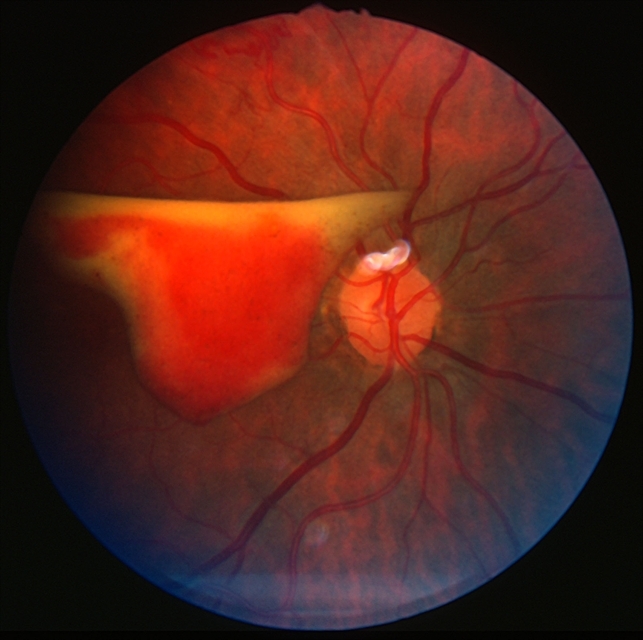

Следует выделить два типа макроаневризм: мешотчатые (в виде выпячивания стенки) и в виде «манжетки». Макроаневризмы или их группы часто находятся в зоне артериовенозного перекреста или бифуркации, преимущественно, располагаясь по верхне-височной ветви центральной артерии сетчатки, значительно реже — по другим артериальным ветвям. При офтальмоскопии на артериоле первого-третьего порядка определяется изолированный, серый, умеренно проминирующий фокус, вокруг которого обычно имеются интраретинальные геморрагии различной величины. Сетчатка в зоне аневризмы отечна и утолщена. Нередко макроаневризма не просматривается под геморрагиями и экссудатом.

Твердый кольцевидный экссудат обусловлен патологической проницаемостью стенок сосудов. Если экссудат и ретинальный отек захватывает макулярную область, то отмечается снижение остроты зрения. Также в зоне макроаневризм выявляется неравномерный калибр артериол, муфты по ходу сосудов, расширение дистального отдела. Иногда в просвете артериолы выявляются холестериновые эмболы.

Разрыв стенок макроаневризмы приводит к суб-, интра-, преретинальным или интравитреальным геморрагиям. Локализация кровоизлияний в основном зависит от разрыва передней или задней стенки аневризмы.

Геморрагии, локализующиеся на глазном дне, имеют различный цвет, который зависит от месторасположения, длительности существования и толщины слоя излившейся крови. Так свежие или тонкие кровоизлияния имеют светло-красный цвет, а старые или массивные — кажутся более темными. Все кровоизлияния можно разделить на преретинальные, интраретинальные и ретроретинальные.

При массивных преретинальных геморрагиях может произойти разрыв гиалоидной мембраны и, тогда кровь, проникая в стекловидное тело, образует интравитреальные кровоизлияния. Через несколько дней, при оседании эритроцитов, офтальмоскопическая картина преретинальных геморрагий изменяется. В это время они состоят как бы из двух частей: более прозрачной полукруглой верхней части розового или бледно-желтого цвета (за счет плазмы) и нижней части в виде темно-красной чаши с четким горизонтальным уровнем. В этом случае цвет обусловлен скоплением эритроцитов.